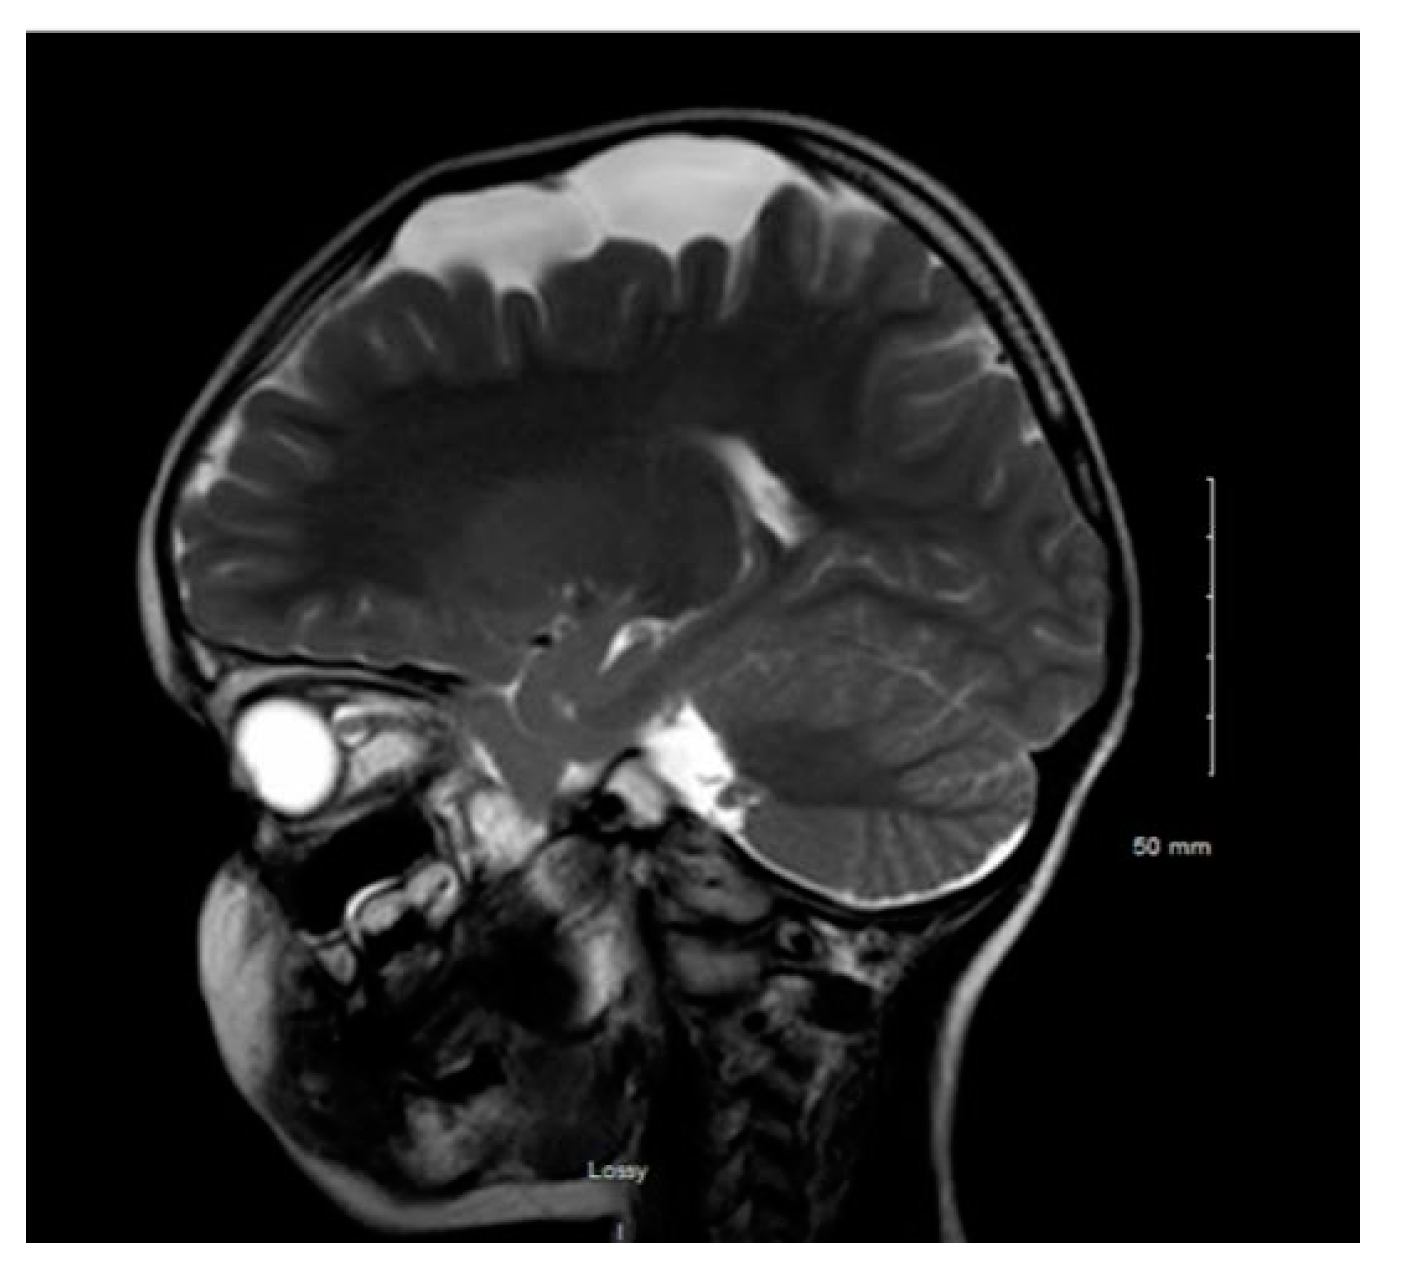

Figure 1. MRI T2WI, sagittal section in 2019 (11 years of age).

Figure 1 and Figure 2 reveal a change in signal of arachnoid cyst suggestive of interval hemorrhage with a thin subdural hematoma along its inferior aspect. Minimal edema in the subjacent Rolandic cortex was present. Given the patient’s stroke-like presentation, an MRA of head and neck was administered, which was found to be normal. The findings, with a comparison of the previous MRI of the patient at age 4 (Figure 3 and Figure 4), are consistent with a ruptured arachnoid cyst. No acute neurosurgical intervention was performed due to the absence of raised intracranial pressure and reduction of neurological symptoms. A routine EEG performed in the emergency department exhibited interictal epileptiform discharges over the left and right central–temporal region during drowsy and sleep states, suggestive of increased risk for partial seizures from these regions.